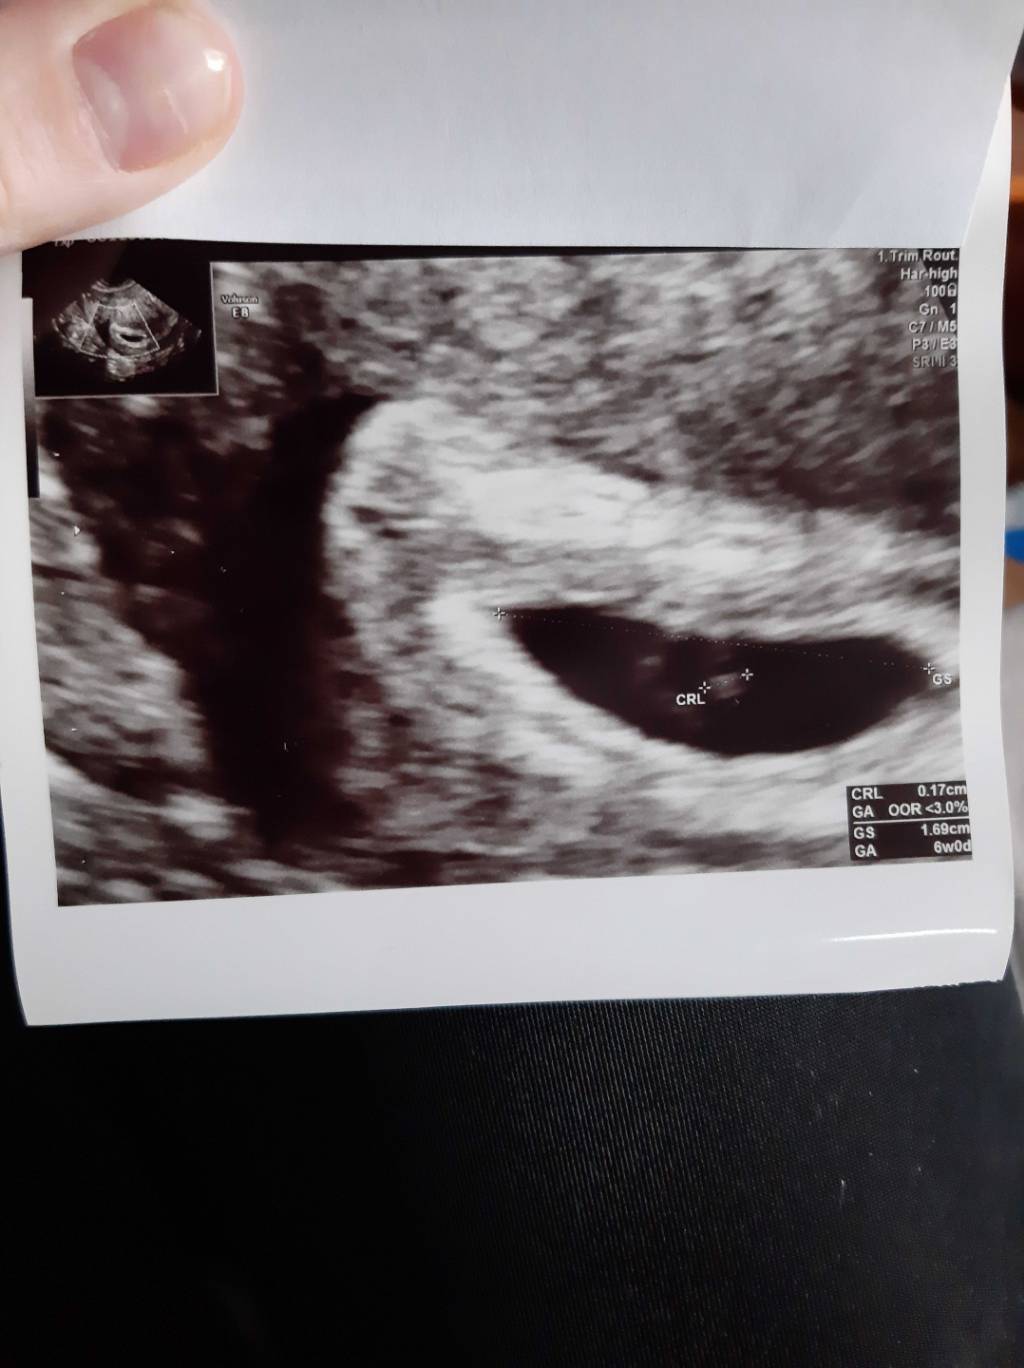

Dziś byłam na usg , bardzo się bałam ... bo od poniedziałku mam plamienie...no i jest nasz cud [emoji173] mam nadzieję że będzie trwał!

Zobacz załącznik 1104096